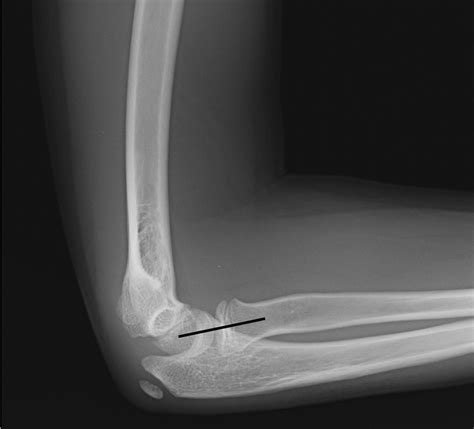

Diagnosing nursemaid elbow typically involves a physical examination by a healthcare provider. The provider will assess the child's arm and elbow for signs of injury and may perform a gentle manipulation to confirm the diagnosis. In some cases, a Nursemaid Elbow Xray may be ordered to rule out other potential injuries, such as fractures or dislocations. However, X-rays are not always necessary for diagnosing nursemaid elbow, as the injury does not typically show up on imaging studies.

In some cases, nursemaid elbow may be mistaken for other injuries, such as fractures or dislocations. It is important to seek medical attention if your child experiences pain or limited movement in the elbow, even if you are not sure what caused the injury. A healthcare provider can perform a thorough evaluation and order a Nursemaid Elbow Xray if necessary to rule out other potential injuries.